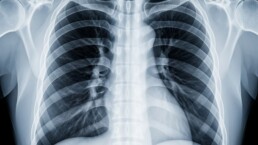

Welttuberkulosetag am 24. März 2025

Tuberkulose bleibt 2025 eine der tödlichsten Infektionskrankheiten weltweit. Für internationale Entsendungen ist das Wissen über Risikogebiete und Prävention essenziell. Durch die Streichung von…